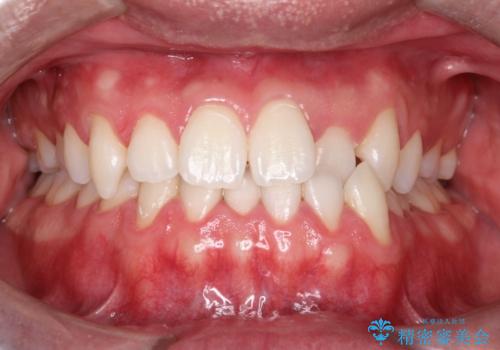

初めてのオフィスホワイトニング

- 結婚式を控えており、ホワイトニングをしたいとのことで来院されました。

全体的に歯石等の汚れが目立っていたためまずはPMTCをおすすめし、行いました。ホワイトニングは初めてということだったため1回の施術で白くなりやすいエクセレントコースをおすすめしました。全体的に汚れを落としたあとにホワイトニングを行ったことにより、薬剤が浸透しやすくなり、1回の施術でも白くなりました。